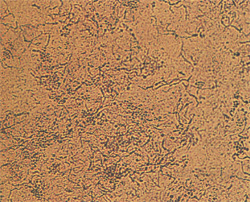

Возбудителем отрубевидного лишая является диморфный липофильный дрожжеподобный гриб. Гриб существует в трех формах: округлая (Pityrosporum orbiculare), овальная (Pityrosporum ovale) и мицелиальная (Malassezia furfur). Две первые формы являются сапрофитными, последняя - патогенной. Установлено, что около 90% здоровых людей являются носителями сапрофитных форм гриба. Излюбленными местами его локализации на теле человека являются волосистая часть головы, верхние отделы туловища и складки. Для перехода возбудителя в патогенную форму и развития заболевания необходимы предрасполагающие факторы: повышенная потливость, уменьшение физиологического шелушения эпидермиса. Возможно, что развитию болезни способствует генетическая предрасположенность. Помимо отрубевидного лишая Pityrosporum ovale вызывает фолликулит и играет основную роль в патогенезе себорейного дерматита. Проявления отрубевидного лишаяКлинически отрубевидный лишай характеризуется мелкими слегка шелушащимися пятнами различных оттенков - от светло-желтого до темно-коричневого. Обычно возбудитель гнездится в устье волосяного фолликула, и в начале заболевания пятна имеют величину булавочной головки, а в дальнейшем они разрастаются по периферии до размеров чечевицы или копеечной монеты, образуя обширные очаги с неровными, фестончатыми очертаниями. Пятна обычно округлой формы и слегка шелушатся мелкими, отрубевидными чешуйками. После солнечного облучения пятна становятся депигментированными и не шелушатся. Излюбленная локализация - кожа верхней части груди, спины в области лопаток, плеч. На кистях и стопах, а также на лице поражения не встречаются. Нередко отрубевидный лишай локализуется на волосистой части головы, без поражения волос. Контагиозность незначительная. Возникновению заболевания способствует потливость. Диагностика отрубевидного лишаяВ диагностике имеет значение проба Бальцера - смазывание кожи пораженных участков раствором йода или метиленового синего усиливает интенсивность окраски пятен. При микроскопическом исследовании чешуек легко обнаруживается возбудитель заболевания в виде кучек круглых спор и коротких нитей. Лечение отрубевидного лишаяНазначение шелушащих и фунгицидных средств. При незначительном распространении показано смазывание пятен 3-5% спиртовым раствором йода или 2-3% йод-салициловым спиртом. При значительном распространении в кожу втирают серно-салициловую мазь. Проводят обработку кожи по способу Демьяновича; применяют производные имидазола (клотримазол, стимазол, фунгизид, лотримин, травоген, микоспор и др.), аллиламинов (ламизил). По окончании лечения во избежание рецидива рекомендуется в течение 2-3 нед обтирать кожу 2% салициловым спиртом или 5% раствором соляной кислоты, облучение УФЛ. А. Н. Poдиoнoв Вся информация в разделе: Заболевания кожи |